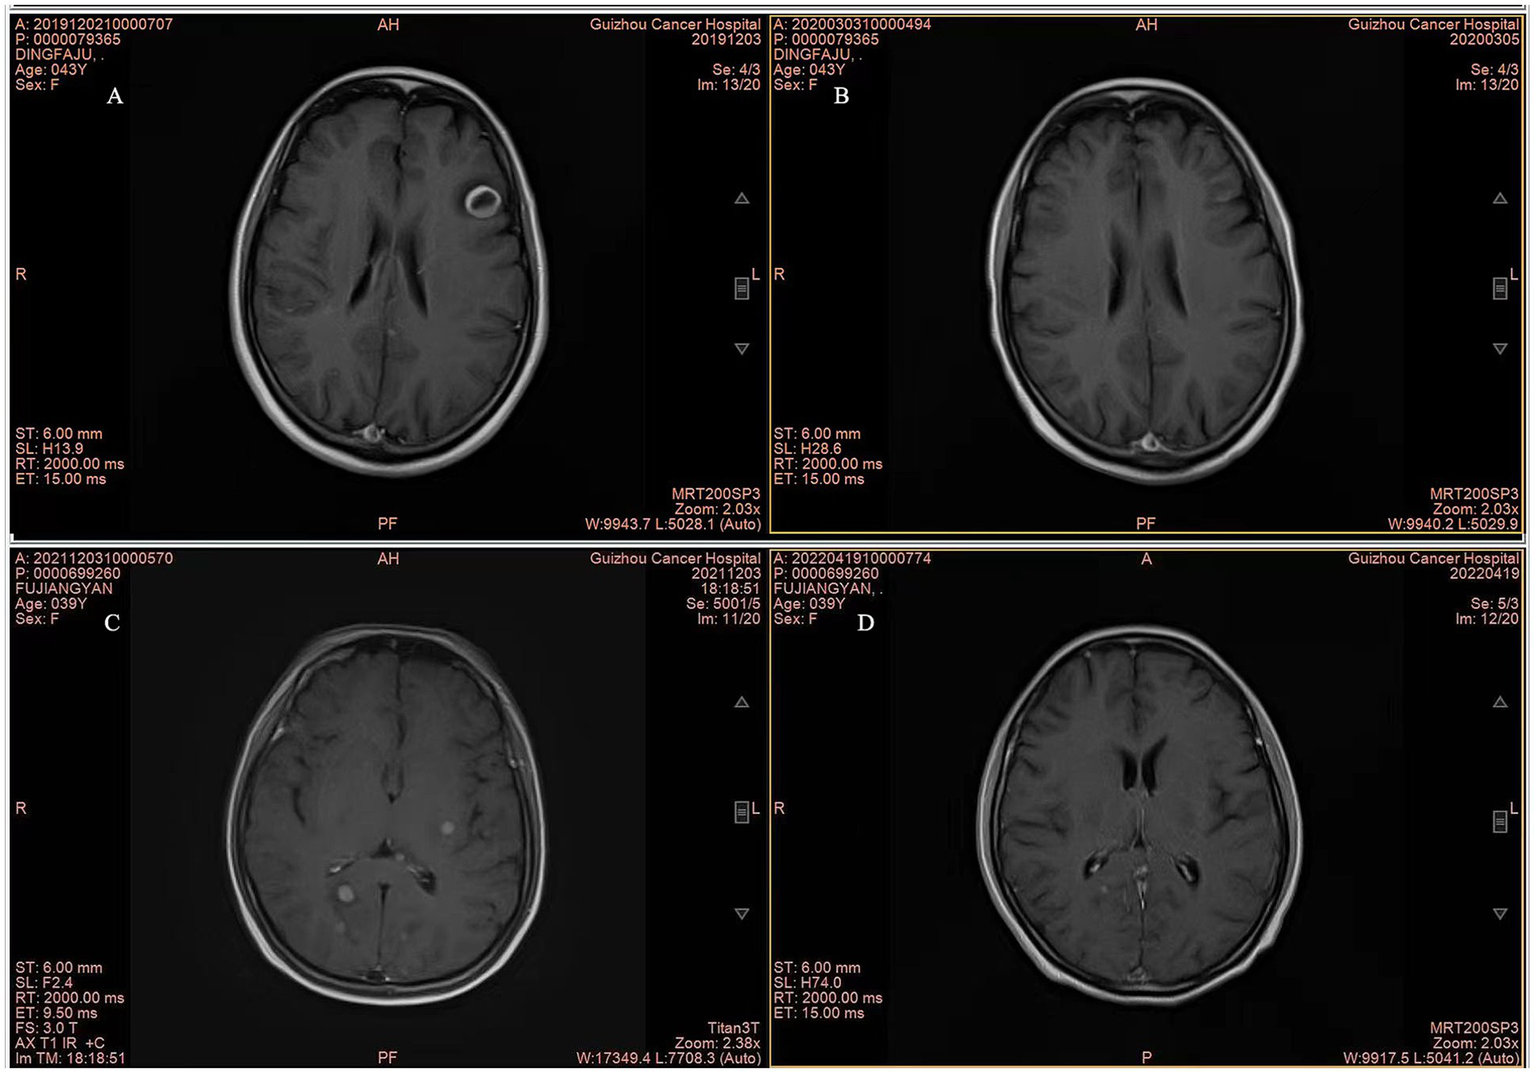

Although the OS data remain immature, there was a significant difference in OS between the WBRT-p and p-WBRT groups (p = 0.02), with a trend of prolonged OS observed in the WBRT-p group (Figure 6). In the WBRT-p group, the OS rates in 1–5 years were 100, 100, 100, 100, and 100%, respectively, while in the p-WBRT group, the OS rates in 1–5 years were 90.0, 80.0, 70.0, 70.0, and 46.7%, respectively. For the overall population, the iORR value was 65.4% (17/26), and the iCBR value was 84.6% (22/26). Notably, no statistical significance was observed between the iORR and iCBR values in the WBRT-p group (63.6%, 7/11, and 90.9%, 10/11) and the p-WBRT group (66.7%, 10/15, and 80.0%, 12/15). As shown in the MRI images, a near-complete response (CR) with mild residual cortical enhancement was observed in the p-WBRT group, with scans taken 4 months apart (Figures 7A,B). Similarly, in the WBRT-p group, a partial response (PR) was observed, also with scans taken 4 months apart (Figures 7C,D). Regarding extracranial response, the extracranial ORR and CBR values were 69.2% (18/26) and 92.3% (24/26) in all 26 patients, 72.7% (8/11) and 90.9% (10/11) in the WBRT-p group, and 66.7% (10/15) and 93.3% (14/15) in the p-WBRT group, respectively (Table 2).

Figure 7

Representative MRI Images of patients. (A,B) MRI images show complete response (CR) in a patient from the p-WBRT group before and after treatment. The interval between the scans was 4 months. The images illustrate the complete disappearance of brain metastases over the course of treatment. (C,D) MRI images show partial response (PR) in a patient from the WBRT-p group, with a 4-month interval between scans. The images demonstrate a significant reduction in the size of brain metastases following the treatment.